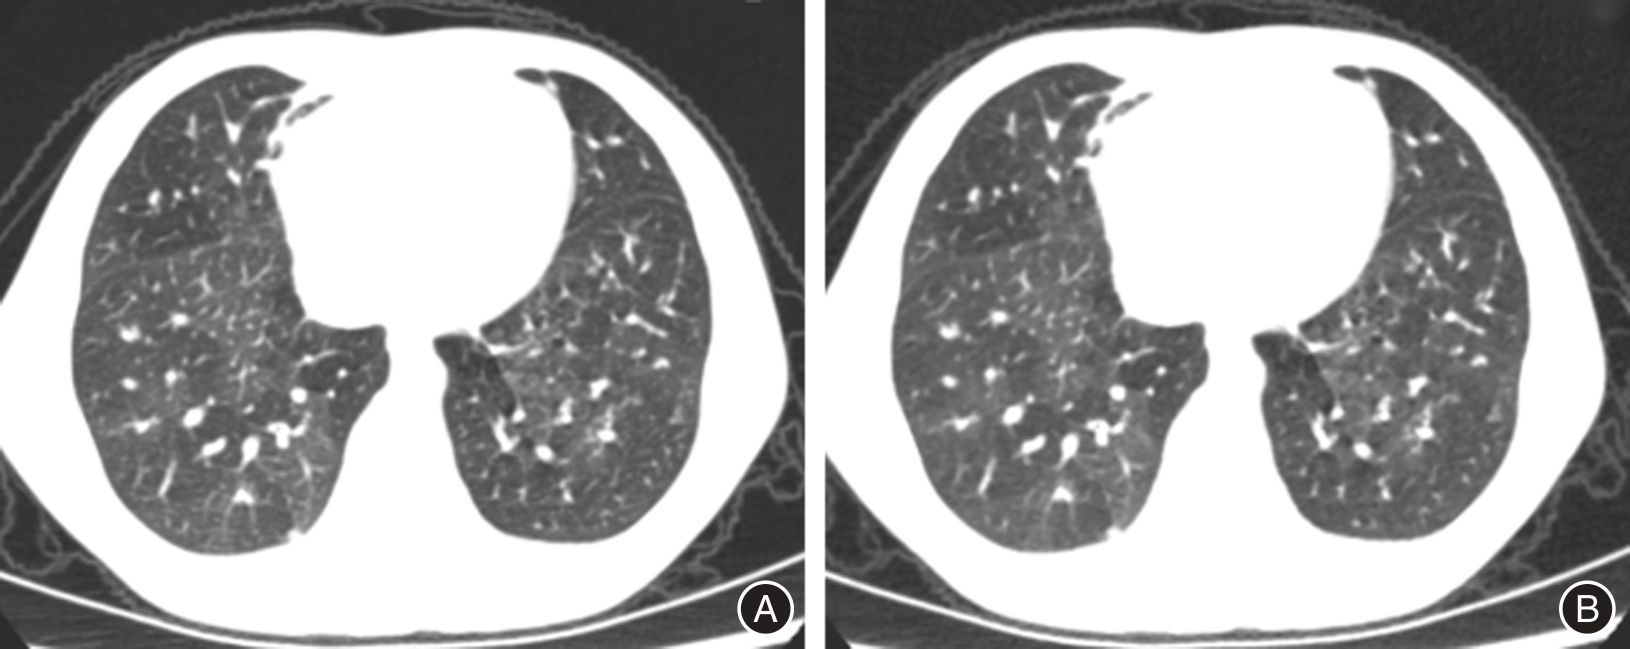

Tab.2

Comparison of subjective image quality between DLIR and ASIR-V"

| 项目 | 1分 | 2分 | 3分 | 4分 | 5分 |

|---|---|---|---|---|---|

| ASIR-V20% | 0(0.00) | 11(6.88) | 19(11.88) | 99(61.88) | 31(19.38) |

| ASIR-V50% | 0(0.00) | 6(3.75) | 13(8.13) | 95(59.38) | 46(28.75) |

| ASIR-V80% | 0(0.00) | 2(1.25) | 7(4.38) | 82(51.25) | 69(43.13) |

| χ2值 | 21.972 | ||||

| P值 | < 0.001 | ||||

| DLIR-L | 0(0.00) | 0(0.00) | 6(3.75) | 116(72.50) | 38(23.75) |

| DLIR-M | 0(0.00) | 0(0.00) | 1(0.63) | 99(61.88) | 60(37.50) |

| DLIR-H | 0(0.00) | 0(0.00) | 0(0.00) | 64(40.00) | 96(60.00) |

| χ2值 | 34.982 | ||||